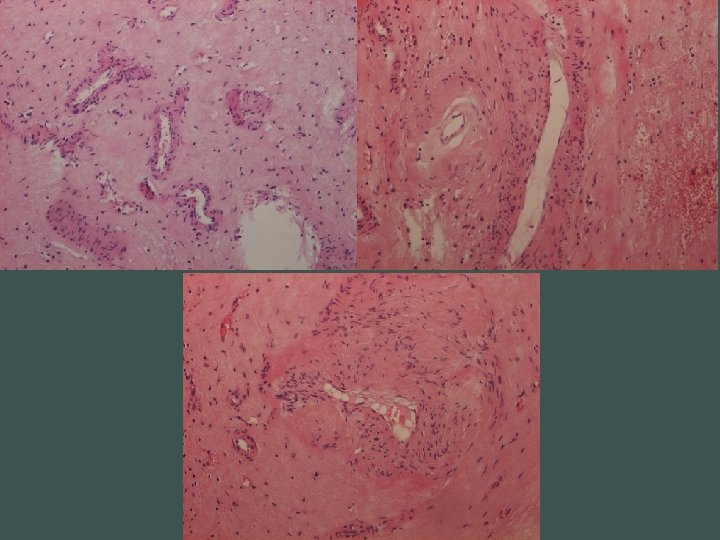

Naša diagnóza Segmentálna atrofia pečene, stage II / nodulárna elastóza pečene

Segmentálna atrofia pečene • zriedkavý pseudotumor • častejšie u žien, unifokálny • najčastejší príznak bolesť horného pravého kvadrantu • prevažne subkapsulárne • 1, 8 - 10 cm • abnormálne hrubostenné cievy (len intralezionálne), často trombotizované, rekanalizované • biliárne cysty

Stage 1 - 4 • 1 – kolaps parenchýmu so zachovaním portálnych polí, občasnými ostrovčekmi zachovaného parenchýmu a s duktulárnou reakciou • 2 – minimálna až žiadna duktulárna reakcia, zvýšená miera elastózy • 3 – takmer výlučne elastóza, občasné malé ostrovčeky hepatocytov • 4 – end stage, ložisko fibrózy

Elastika? • v poškodených tkanivách sa môže tvoriť nadmerné množstvo (dezorganizovaných) elastických vlákien • v pečeni normálne v stenách ciev, malé množstvo v portálnych poliach a okolo centrálnej vény • pri poškodení produkujú portálne fbroblasty • prečo tak exuberantne?